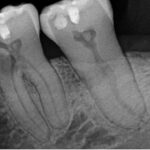

At our endodontic practice in St. Petersburg, Florida, we often treat patients with root resorption, a condition where parts of a tooth’s structure start to break down. In most cases, this happens to a single tooth. But sometimes, we see something more unusual: bilaterally symmetrical resorption. That means the same teeth on both sides of the mouth are affected, often in similar ways.

Over several years, we followed a patient with resorption in the same three teeth on both the left and right sides. Here’s how it progressed:

- The first molars on both sides had the largest areas of damage. The resorption was located on the cheek side (buccal) of the mesial root and extended into the furcation, the space where the roots meet. Because of the size of the lesions, root canal treatment (RCT) was necessary for both molars.

- The bicuspids (premolars) and cuspids (canines) also showed signs of resorption, but the damage was much smaller. These teeth did not need root canals.

We used a full-mouth scan to monitor this case. While this gave us a broad view, it doesn’t provide the same fine detail as a limited field of view scan. There were some artifacts (image distortions) from previous repairs on the right side, but the left side images were clearer.